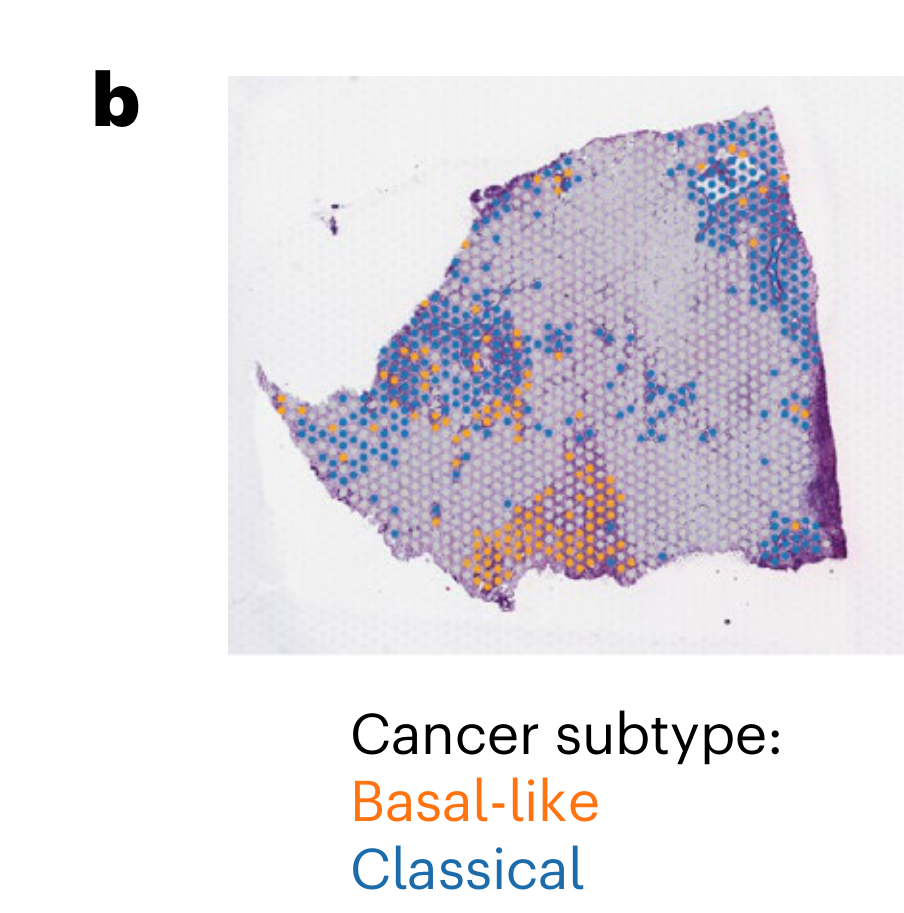

Zohora F.T. et al. - 2025

CellNEST reveals cell–cell relay networks using attention mechanisms on spatial transcriptomics

Condition Dimension

Categorical

Data Components

Gene Expression Matrix

Data

Modality

Sequencing-based

Resolution of observation

Multi-cellular

Visualized Elements

FeatureObservation

Biological

Tissue

Abstraction

Partial

Chart Type

HexplotScatterplot

Communicative/Contextualization

Reference structure

Comparative Design

Juxtaposition : Small multiples

Layout

Spatial : Physical

Scalability Strategy

None (Item-level)

What is the spatial distribution of disease subtypes?

What is the tissue morphology and architecture?